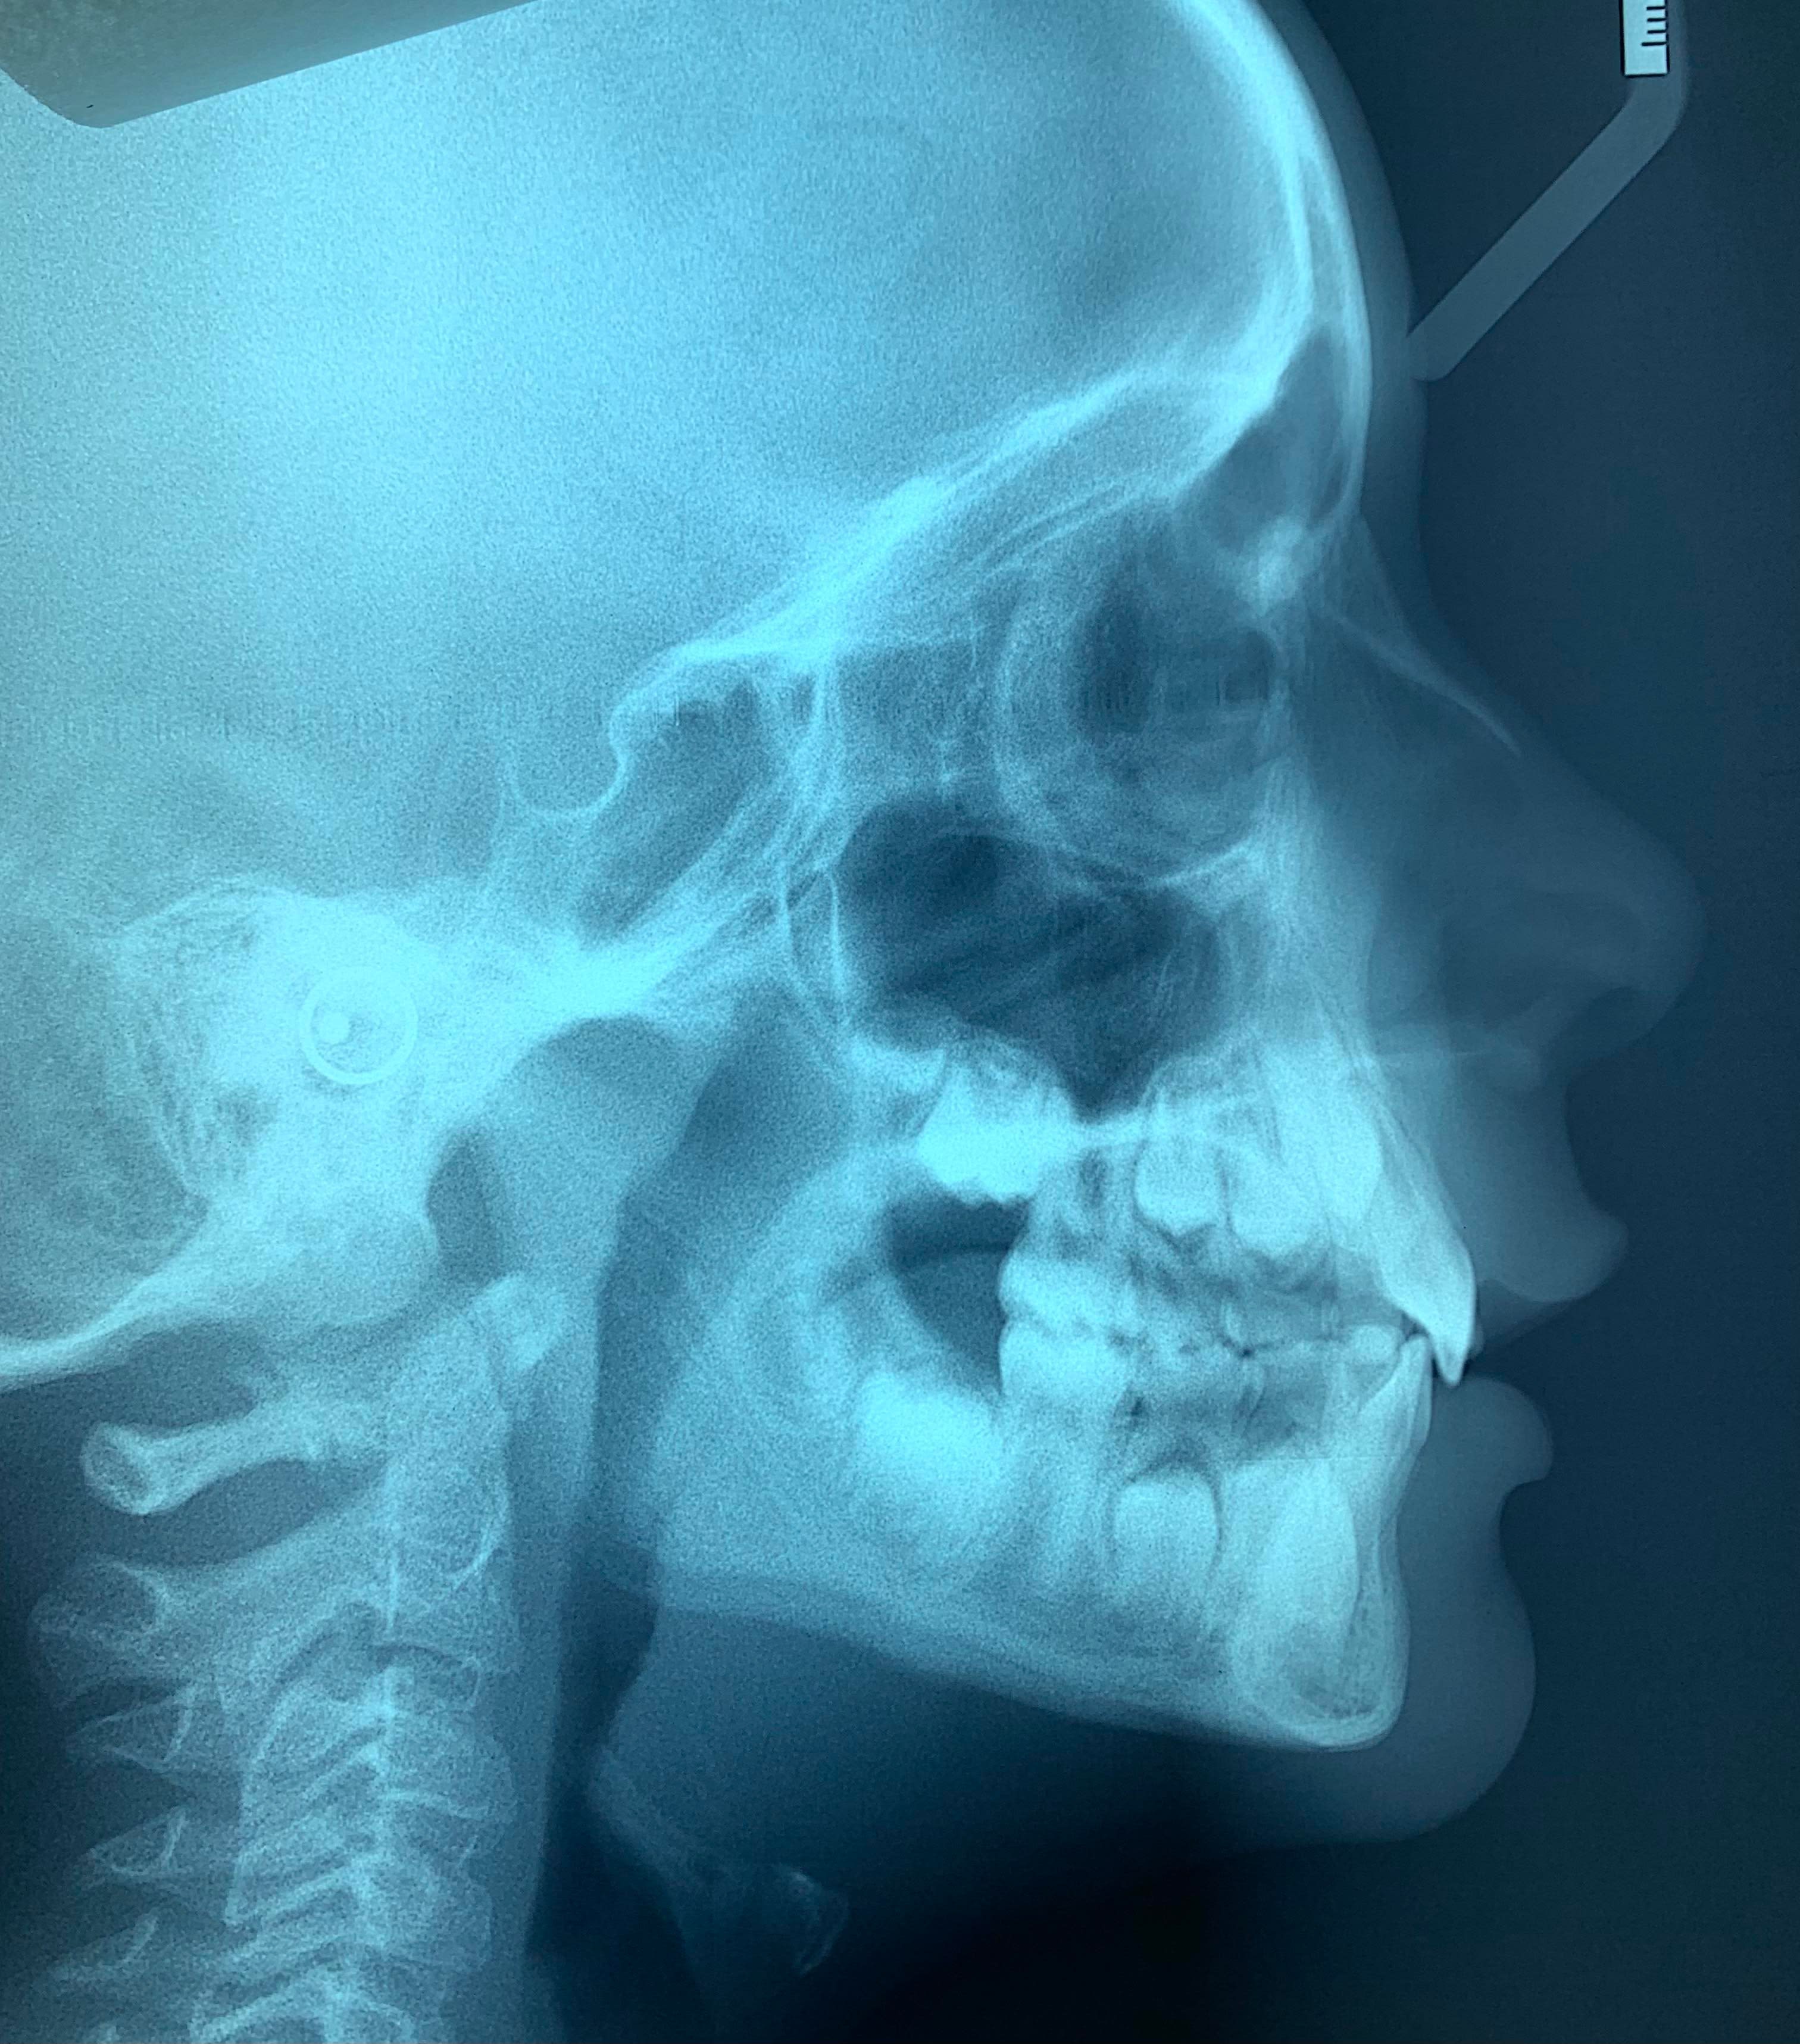

Normodivergent, classe I squelettique

Retroalveolie incisives centrales supérieures

DDM : signe de quintero maxillaire, 32 lingualee, manque d’espace

Classe 1 molaire, plan terminal de Chapman à marche mesiale

DDM antérieur (32 à 42) mesurée à 5mm, l’espace disponible du secteur moyen (III-IV-V) devrait, après calcul, être entièrement consommé par l’espace nécessaire à l’évolution des 3-4-5 définitives.

Pas d’inverse d’occlusion, distance 6-6 maxillaire = 35mm. Inclinaison coronolinguale des procès alvéolaires

Arcade maxillaire plutôt rectangulaire.

Il y a peut-être une incompétence labiale mais avec uniquement la téléradio pour les tissus mous c'est difficile à dire.